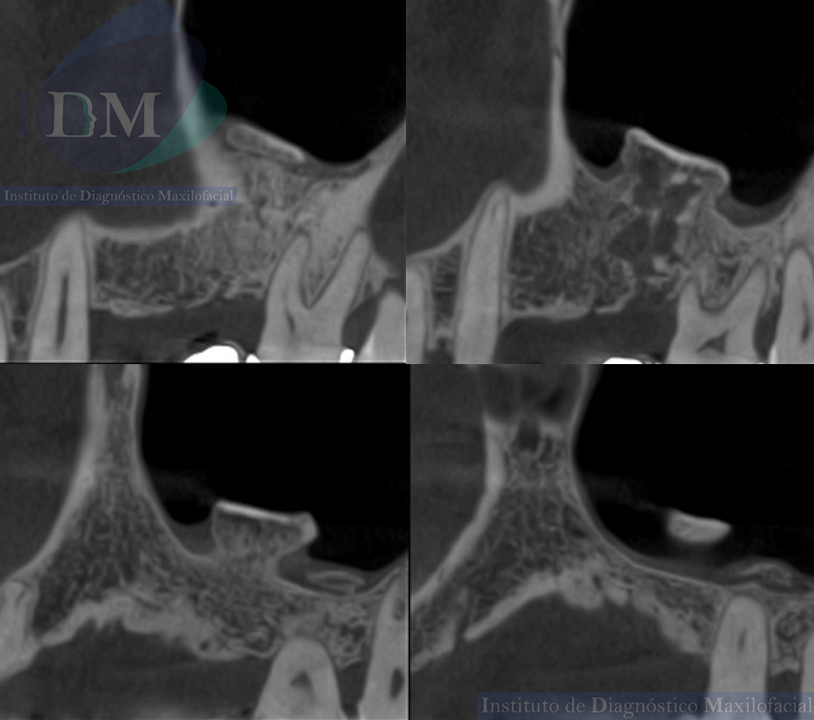

A la evaluación de la tomografía computarizada de haz cónico (TCHC) en los cortes axiales, transaxiales y en la reconstrucción 3D se observa una estructura ovalada hiperdensa heterogénea con contenidos mixtos irregulares localizada en piso del seno maxilar izquierdo con extensión hacia el antro sinusal. Además, en las imágenes tangenciales se observa la presencia de un antrolito adyacente a nivel de la pieza 26.

CORTES TRANSAXIALES